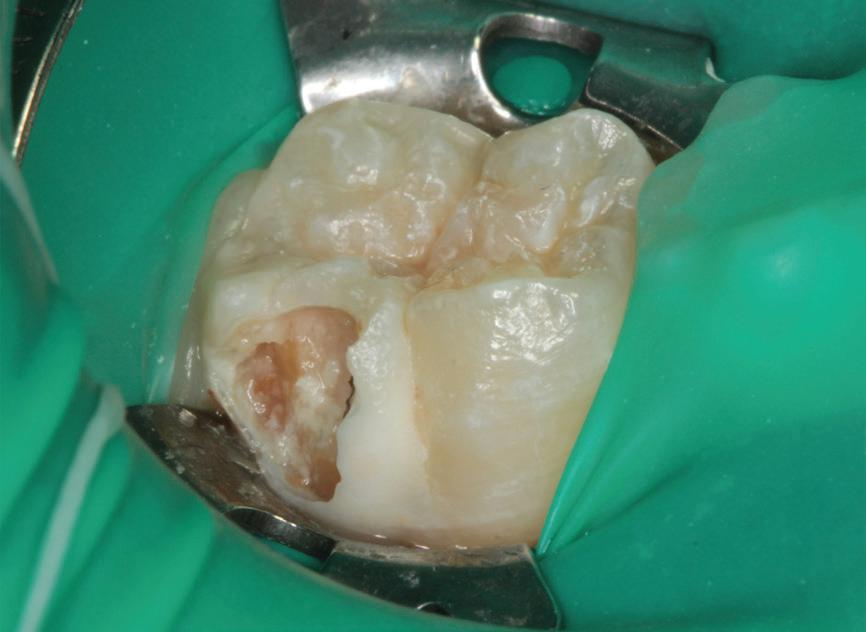

After establishment of local anesthesia and rubber dam isolation, the SSC, the Vitrebond layer, and the Biodentine layer were removed. A hard tissue barrier was found, and an access opening into the pulp chamber was created with a high-speed round diamond bur used with water coolant. Slight bleeding from the visually pale pulp tissue was observed; therefore, CP was performed by removing the pulp tissue from the orifices using a sterile high-speed round diamond bur with water coolant and spoon excavation. The radicular pulp tissue had a resilient texture and bright red blood with continuous flow, suggesting that the pulp was healthy and vital (Fig 9). Next, 2.5% NaOCl was used for pulp wound irrigation, and hemostasis was achieved within 6 minutes by applying cotton pellets soaked in 2.5% NaOCl. Afterward, the pulp tissue and coronal portion of the tooth were irrigated with normal saline solution

Fig 9. Clinical evaluation showing bright red bleeding, suggesting a resilient pulp.